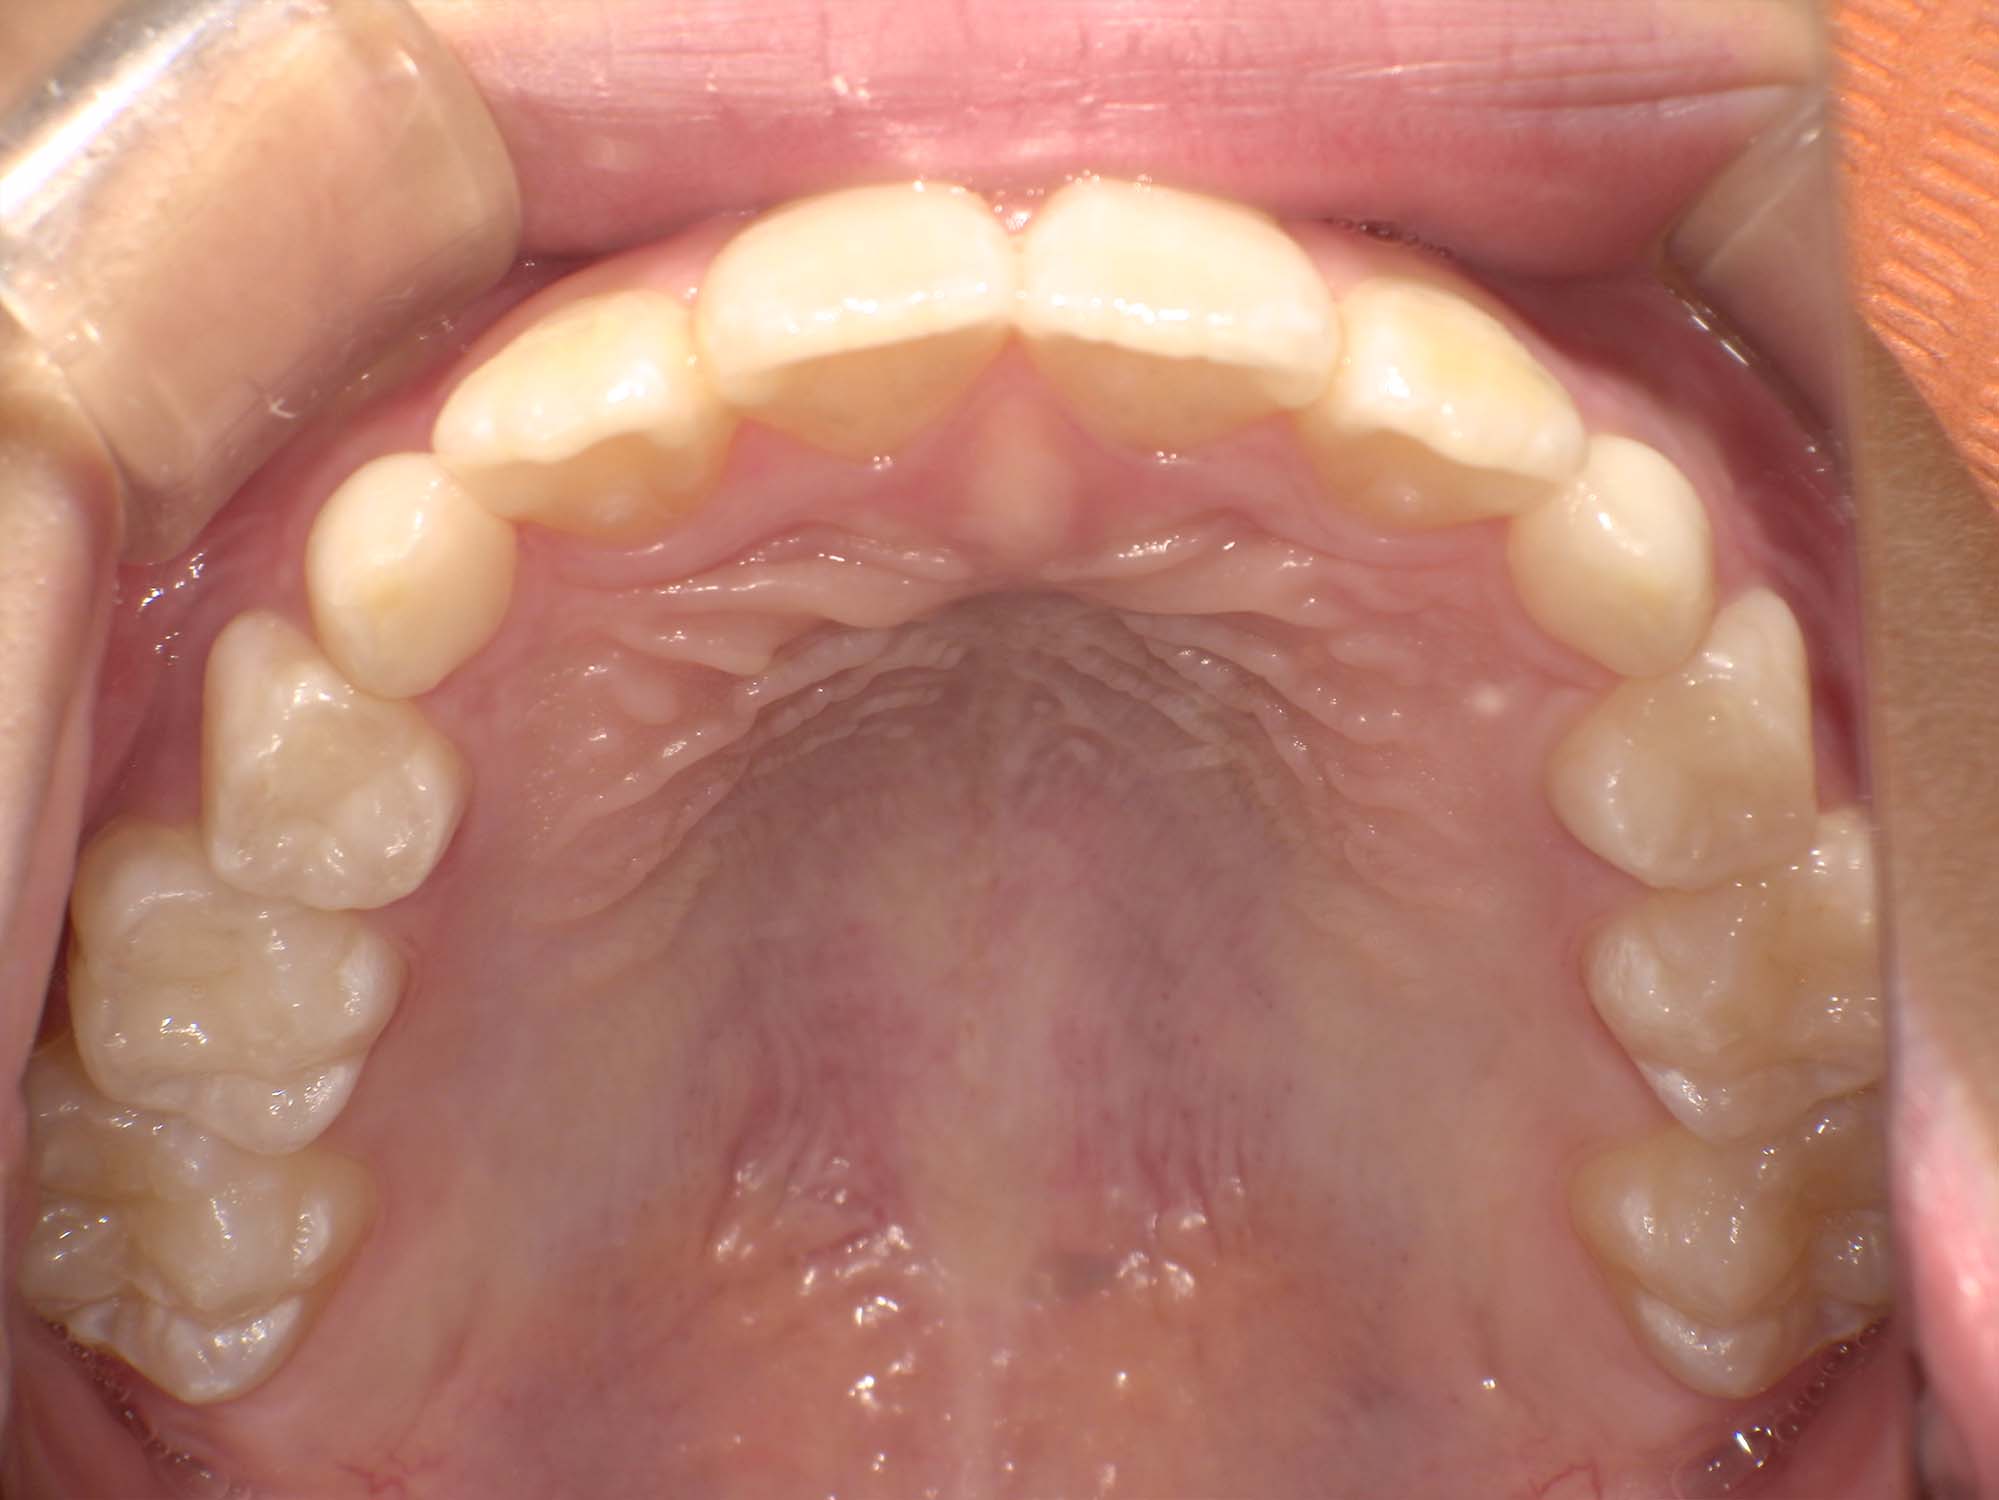

| 年齢・性別 | 8歳9ヶ月の女児 |

|---|---|

| 主訴 | 歯並びの乱れを気にされて来院された患者様です。将来的なスペース不足と歯のねじれ(翼状捻転)が懸念されました。 |

| 治療期間・回数 | 2年10ヶ月・19回 |

| 費用 | 430,000円(税別) |